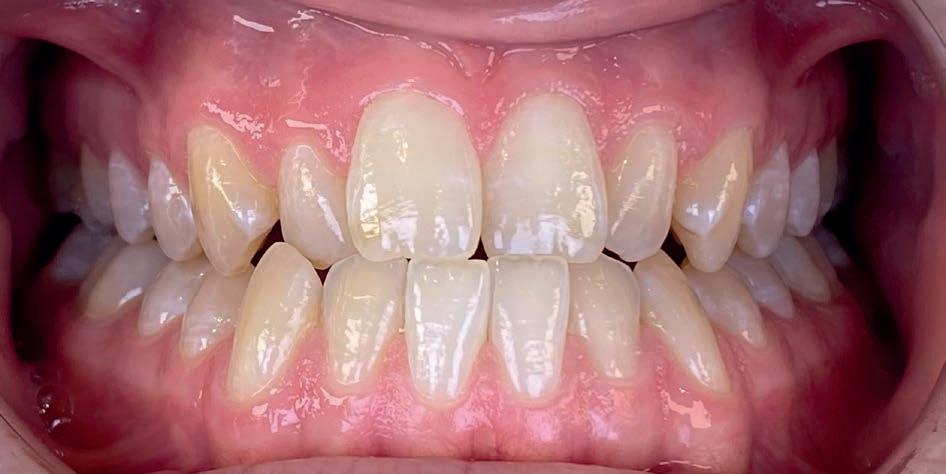

Resultaat

• Klasse I-occlusie

• Harmonieuze lachlijn en verbrede tandbogen

• Geen extracties

• Profiel en gezichtsbalans behouden

Retentie: Vaste spalk boven én onder, aangevuld met een nachtbeugel

“Door ruimte te creëren met een D-gainer in plaats van tanden te trekken, blijft het profiel natuurlijk en ontstaat een bredere, stabiele tandboog.”